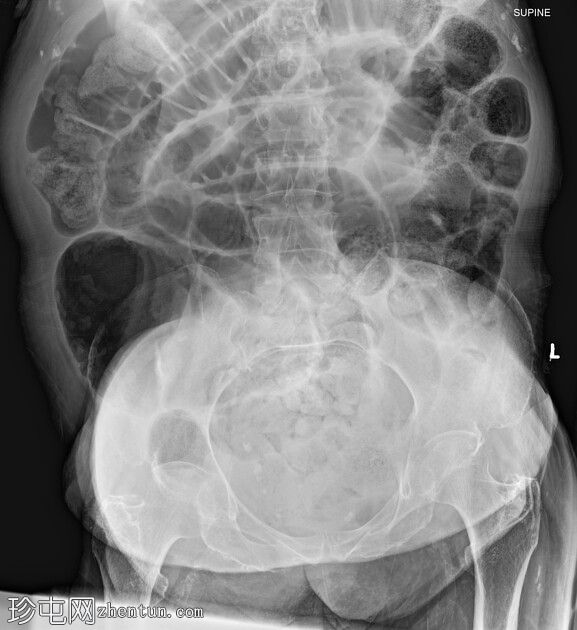

CT

轴位平扫

大肠内可见中度粪便。横结肠轻度扩张(约6.6厘米)。

数处小肠袢直径接近临界值(约3厘米),部分肠袢内可见粪便。

腹部中央及右侧可见数处小肠袢肠壁明显变薄,并可见肠壁积气。

少量腹水。

主动脉及其内脏分支可见明显动脉粥样硬化。肠系膜上动脉(SMA)开口处中度至重度狭窄;但开口后显影良好。

目前未见明显的门静脉-肠系膜静脉积气。

无气腹。